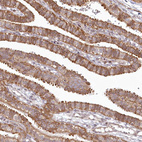

Immunohistochemical staining of human small intestine shows strong cytoplasmic positivity in glandular cells.